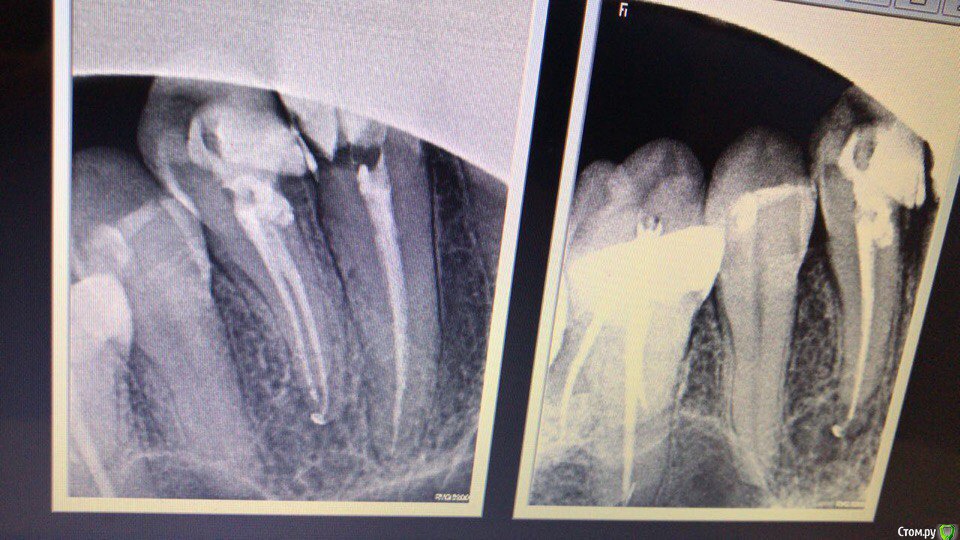

1586Doc Опубликовано 24 февраля, 2018 Автор Поделиться Опубликовано 24 февраля, 2018 (изменено) как-то так) Изменено 24 февраля, 2018 пользователем 1586Doc 1 Ссылка на комментарий